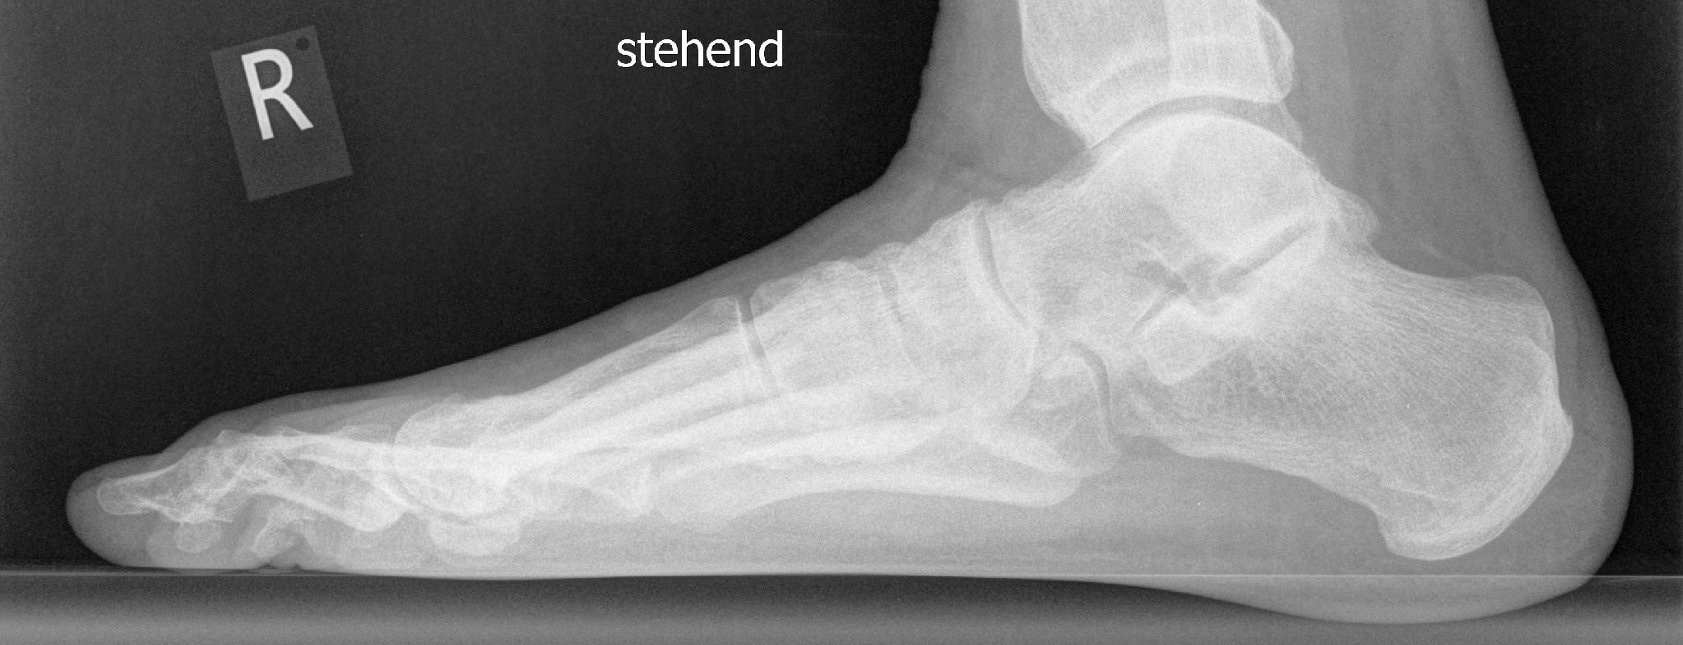

Um festzustellen, ob eine Hallux valgus-Deformität vorliegt, erfolgen zunächst ein Anamnesegespräch sowie eine ausführliche Untersuchung beider Füße in stehender Position. Häufig ist die Erkrankung dabei schon deutlich zu erkennen. Zur Planung der Therapie kommen darüber hinaus Röntgenaufnahmen des betroffenen Fußes zum Einsatz. Eine Schnittbilddiagnostik (CT, MRT) ist in der Regel nicht erforderlich.